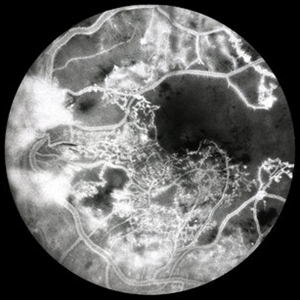

PDR with Severe Subhyaloid Hemorrhage

PDR with severe subhyaloid hemorrhage sparing fovea CF.

Condition/keywords: subhyaloid hemorrhage